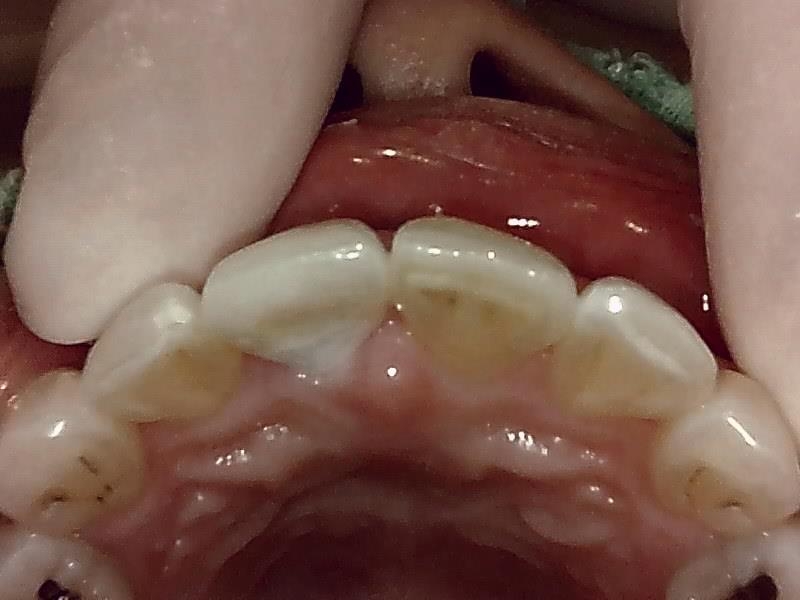

ジルコニアセラミック冠の装着前の支台歯形成(写真)